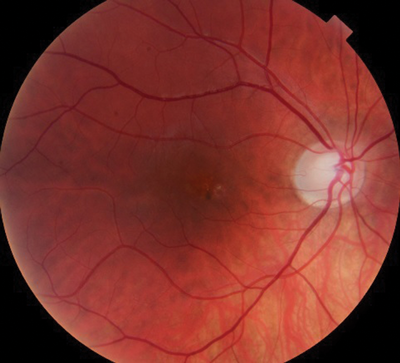

On ocular examination, visual acuity was 6/6 in both eyes (BE). Anterior segment and intraocular pressure were normal. Fundal assessment revealed a characteristic lesion in the macular area in the right eye shown in Figure 1a. Figure 1b shows the corresponding optical coherence tomography (OCT) image of the lesion. Left eye (LE) fundus was unremarkable.

Figure 1b: RE OCT.

1. Figure 1a shows an area of retinal pigment epithelium changes associated to a surrounding well-defined round area of serous macular elevation. The fluid is occupying the space between the photoreceptor layer above and retinal pigment epithelium (RPE) below called subretinal space. Given the young age of the patient, the unremarkable medical history but the underlying stress, and the clinical features the most likely diagnosis would be central serous retinopathy (CSR). The most accepted current theory to explain the pathophysiology of CSR is a combined dysfunction of both choroid and RPE resulting in focal choroidal hyperpermeability and eventual accumulation of fluid in the subretinal space.